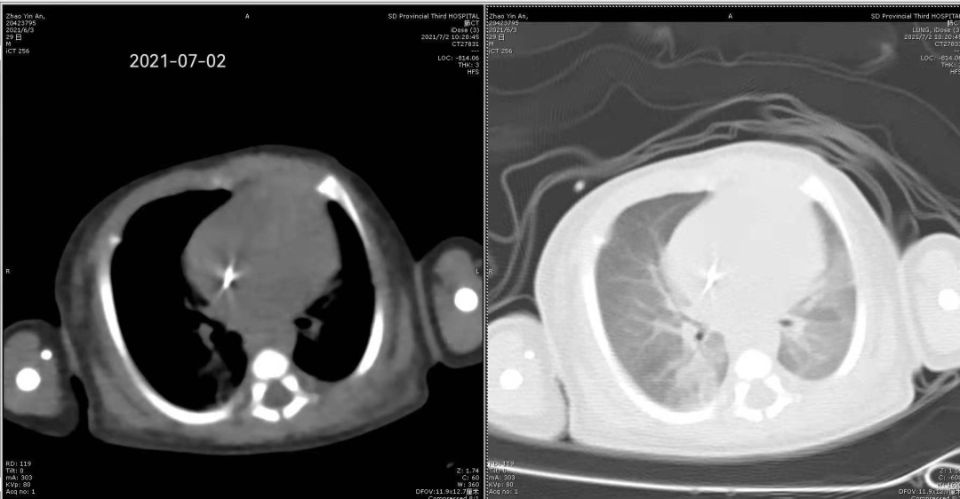

儿科王祥宇医生在新生儿病房为患儿实施了床边纤维支气管镜检查及肺泡灌洗术。术中采用局部麻醉下经鼻孔进镜,仔细探查患儿气管、支气管等情况。左肺下叶基底段可见较多粘痰样分泌物,管腔内可见粘痰样分泌物堵塞,通气不佳,给予分次灌洗,并收集灌洗液进行病原学检测。术中密切监测患儿生命体征,手术过程顺利,患儿生命体征平稳,无不良反应。大家都为这个幼小而强大的生命松了口气。

该例早产危重症患儿的成功救治,标志着医院新生儿科急危重症救治水平又迈上了一个新台阶。此类技术的成功开展也为新生儿重症肺炎的恢复提供了有力的技术保障。